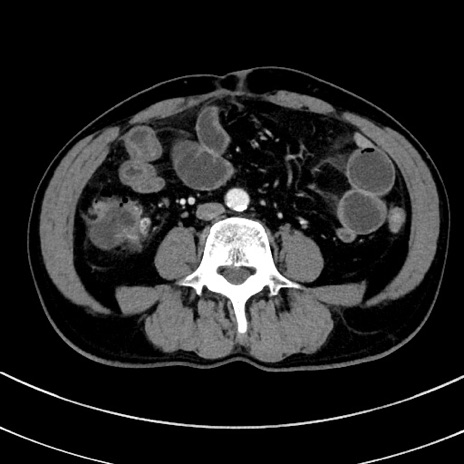

症例8(横断像)

【症例】 60歳代男性

【主訴】 黒色吐物

【現病歴】 4日前から嘔気自覚、2日前の朝食後にも嘔気あり、自分で手で嘔吐反射起こし嘔吐したところ血が混ざっていたため受診。

【既往歴】 5年前汎発性腹膜炎を伴う急性虫垂炎で手術、高血圧、前立腺肥大症、高脂血症

【身体所見】 腹部正中に手術癩痕あり 腹部平坦・軟圧痛なし膨満感あり

【データ】WBC 8400、CRP 4.54